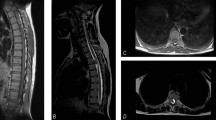

To report a case of a woman with paraplegia who had ruptured ectopic pregnancy but presented with minimal non-specific symptoms and no clinical signs. A trans-vaginal scan confirmed the diagnosis and an emergency laprotomy was performed to save the patient's life.

The diagnosis of ruptured ectopic in spinal cord injury woman can be difficult due to the lack of classical signs and symptoms. Awareness and constant vigilance is required to detect the early signs. Clinicians looking after such women should have sound knowledge of nervous system diseases and their pathophysiology. There should be a high index of suspicion when managing such cases and a prompt surgical treatment should be initiated.